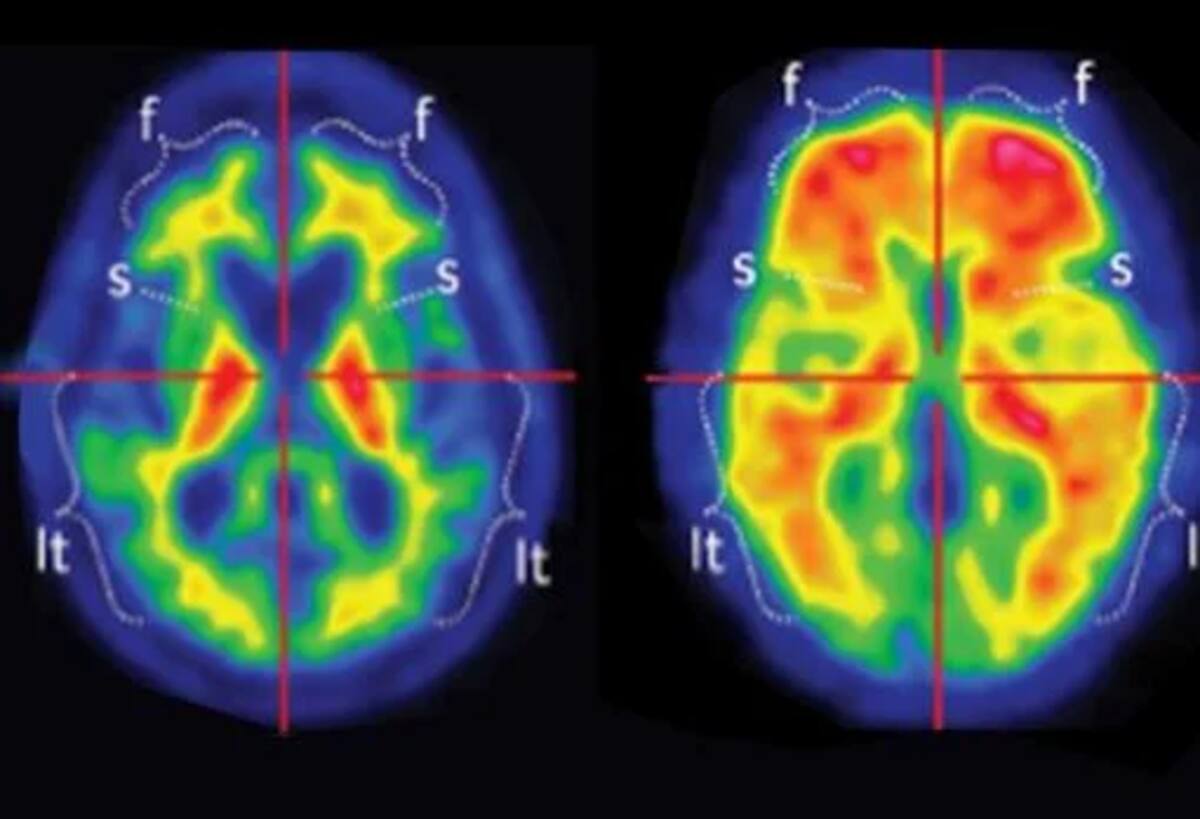

Os estudos de neuroimagem foram cruciais para o diagnóstico. A tomografia por emissão de pósitrons (PET) e a ressonância magnética com fluorodesoxiglicose 18F mostraram;Atrofia hipocampal bilateral e hipometabolismo bilateral do lobo temporal“, conforme indicado no portal Diários SAGE. O hipocampo, necessário para a formação da memória, foi significativamente reduzidoUm achado confirmado por ressonâncias magnéticas mostrando sua redução. Além disso, os córtices parietal e temporal, importantes para o pensamento crítico, também mostraram redução no tamanho visível.

Os sintomas cognitivos do jovem refletiam a gravidade da lesão cerebral. Sua memória geral era uma 82% menor do que amigos de sua idade, e sua memória imediata é uma 87% de desconto. Ele lembrou apenas 37 palavras em cinco tentativas imediatas, em comparação com o normal de 56 para sua faixa etária, e apenas duas palavras 30 minutos depois, quando eram esperadas 13. Este profundo défice o impediu de terminar o ensino médio e foi transferido para uma clínica de cuidados de memória.